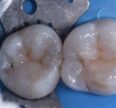

Bonded Dental Crowns

BREAD and BUTTER. One of the few instances where I do full “crowns”. #IPSemaxMT #TheShinEffect